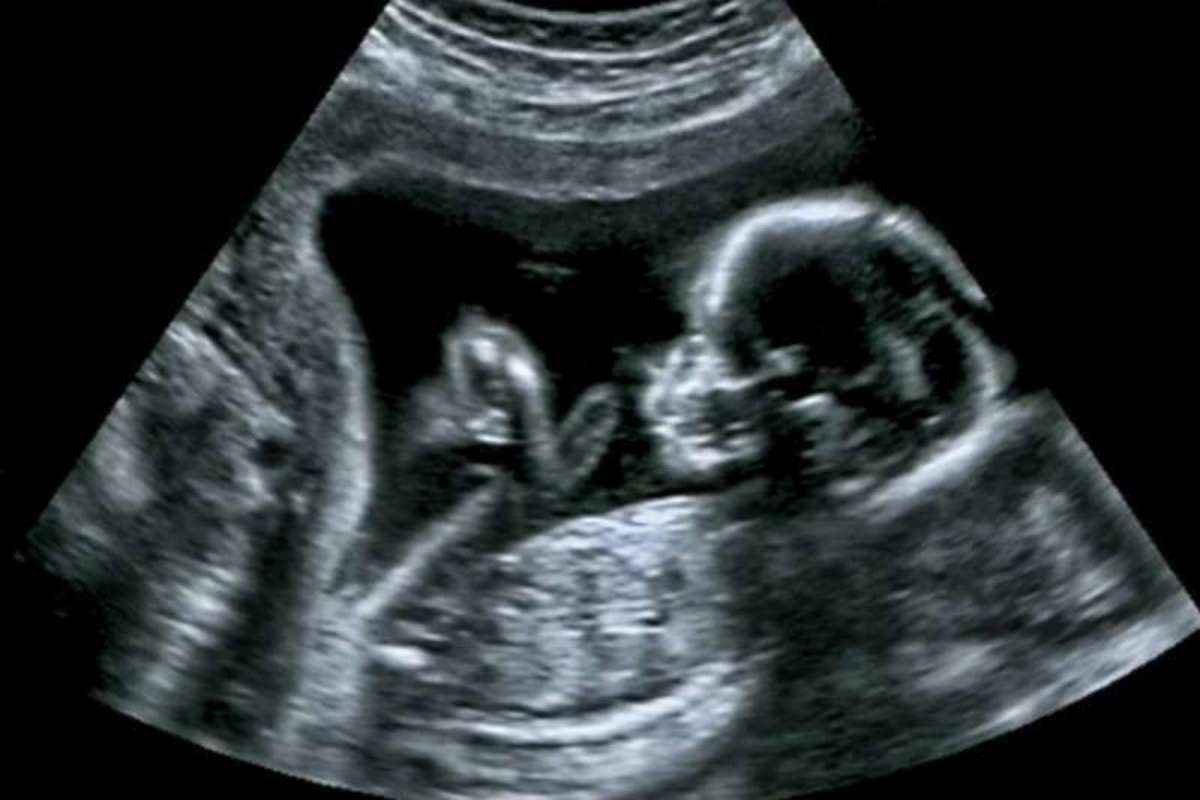

• يٌعرف فحص موجات فوق الصوتية بالسونار وهو من أشهر أنواع فحص نوع الجنين، ويستخدمه الطبيب في تحديد النوع بدءً من الشهر الرابع.

• يتضمن هذا الفحص صورة واضحة للجنين في رحم الأم تتيح معرفة نوع الجنين.